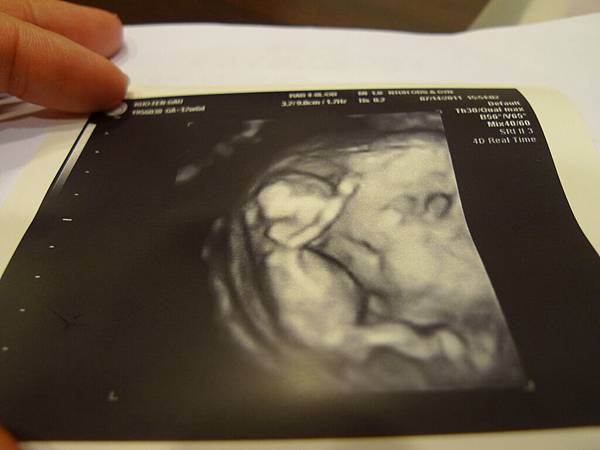

2011.9.1 這一天

我到台大醫院看羊膜穿刺報告

很開心肚子裡的寶貝一切健康

當醫生說:"是女生!!"的時候

媽媽我的確失望了...

crystalkao 發表在 痞客邦 留言(0) 人氣(36)

今天回去台大醫院找我的醫生!!!

蘇醫生幫我算了預產期是101.1.20這下可能會遇到過年期間

突然間我又希望自己可以提早一星期生產 以免遇到蘇醫生部在台北 嗚嗚

現在是第九週 不知道這種反胃噁吐的日子還得過多久 懷孕真的好辛苦 嗚嗚

今天寶寶有心跳了喔 crystalkao 發表在 痞客邦 留言(0) 人氣(66)